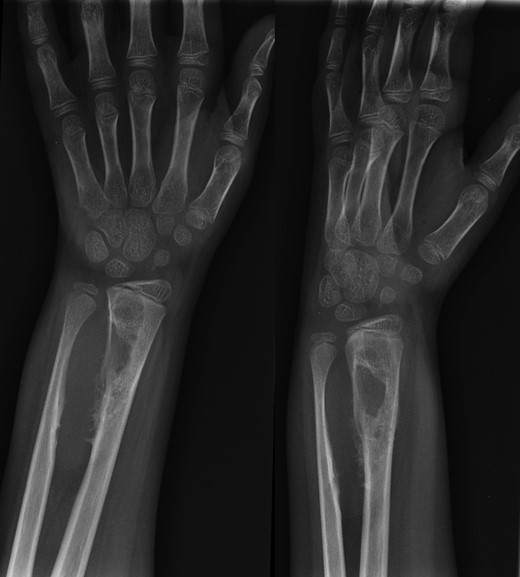

A 10-year-old male was referred to our office after being seen by a pediatric orthopedic surgeon for a distal left forearm mass with block in pronation and supination. The patient's past medical history is significant for a distal radius fracture 2 years prior to his aforementioned office visit. Follow-up radiographs after fracture union at that time showed no evidence of disease (Fig. 1). Radiographs taken at the time of presentation 2 years after fracture healing revealed a 6.5 cm long lesion in the distal syndesmosis arising from the radius. The lesion resulted in pressure erosions upon the distal radius and ulna, causing a slight splaying of the bones (Fig. 2).

Lateral, oblique and anteroposterior (AP) views of distal radius fracture 2 years prior to presentation of desmoplastic fibroma.